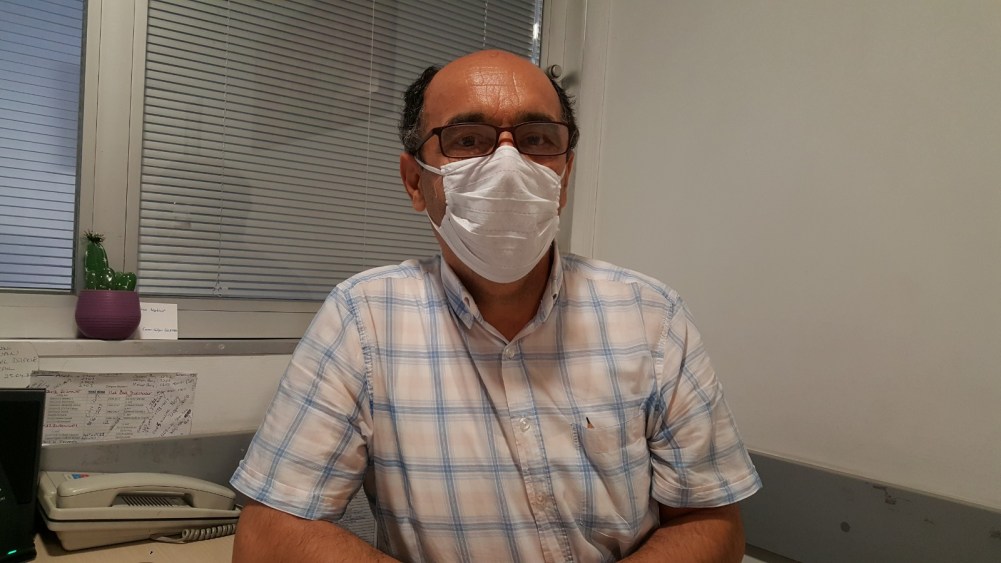

Zonguldak'ın Ereğli ilçesinde 1 yaşındaki D.D.Ç, yuttuğu madeni parayı acil serviste doktorların müdahalesi sırasında kusarak çıkardı. Doktor Nevzat Çimenoğlu, ailelerin bu tür durumlarda yapılacak ilk müdahaleyi iyi bilmeleri gerektiğini ifade ederek, "1 yaşına kadar olan bir bebekse ayaklarından tutup yukarı kaldırıyoruz. Ayrıca sırtına vurarak hava yoluyla atmaya çalışıyoruz" dedi.

Doktor Nevzat Çimenoğlu, çocuklarda yabancı cisim yutma durumunu sıklıkla yaşadıklarını söyledi. Ailelerin böyle bir durumda karşılaşmaları halinde yapacakları ilk müdahaleyi anlatan Dr. Çimenoğlu, "Böyle durumlarda ne yapılması gerekiyor? Önce telaşlanmayacağız. Kesinlikle telaşlanılmaması gerekiyor. İkincisi hemen 112 Acil'in aranması gerekiyor. Ambulansı gelinceye kadar ilk yardım yapılması gerekiyor. Eğer bu hastamız 1-2 aylık bir bebekse, 1 yaşına kadar olan bir bebekse ayaklarından tutup yukarı kaldırıyoruz. Ayrıca sırtına vurarak hava yoluyla atmaya çalışıyoruz. Yetişkinlerde bizim yapmamız gereken valsalva manevrası dediğimiz, akciğer içerisindeki o havayı hızla dışarıya attırmamız lazım. O havada önündeki yabancı cismi dışarı atması lazım. Yetişkinlerde sırtına vurarak çıkartmak mümkün değildir. Bu manevrayla çıkarttırmaya çalışıyoruz" dedi.

Yabancı cismin yemek borusunu geçerek mideye gitmesi durumunda doğal yollarla çıkmasını beklediklerini ifade eden Dr. Çimenoğlu, şöyle dedi:

"Yabancı cisim mideye indiyse yani yemek borusundan doğru mideye gittiyse bizim için çok çok daha az tehlikeli. Büyük abdest, dışkıyla çıkma ihtimali büyük oranda oluyor. Ancak keskin bir cisim ise tabii ki tehlikeli ama esas sıkıntı nefes yoğunluğu gırtlağı tıkarsa ya da nefes borusuna giderse o zaman çok tehlikeli oluyor. Özellikle bebeklerdeki en sık karşılaştığımız şeyler bu küçük oyuncak parçaları. Okul çağındaki çocuklarda da en çok tükenmez kalemin üstündeki tıpa gibi cisimlerin yutulmasıyla da çokça karılaşıyoruz."